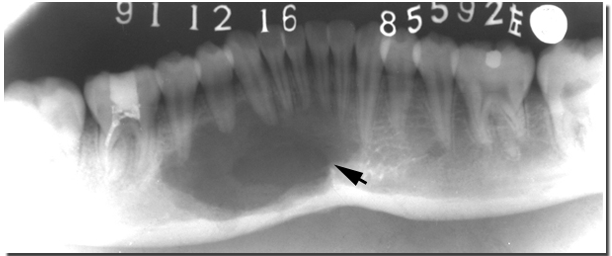

静止性骨囊肿(static bone cyst)实际上是发生于下颌骨后份舌侧的解剖切迹,它是由于发育过程中,涎腺和其它软组织的增殖或迷入而引起的下颌骨局限性缺损。X线片上可表现为囊肿样透射区。有时还可双侧同时发生。这型假性囊肿一般无症状,多在X线检查时偶然发现。好发于下颌磨牙及下颌角区,多位于下齿槽神经管的下方,X线表现为边缘致密的卵圆形透射区。组织学观察,骨缺损区不存在明显的囊肿,可见到涎腺组织、脂肪组织、纤维结缔组织和肌肉等。